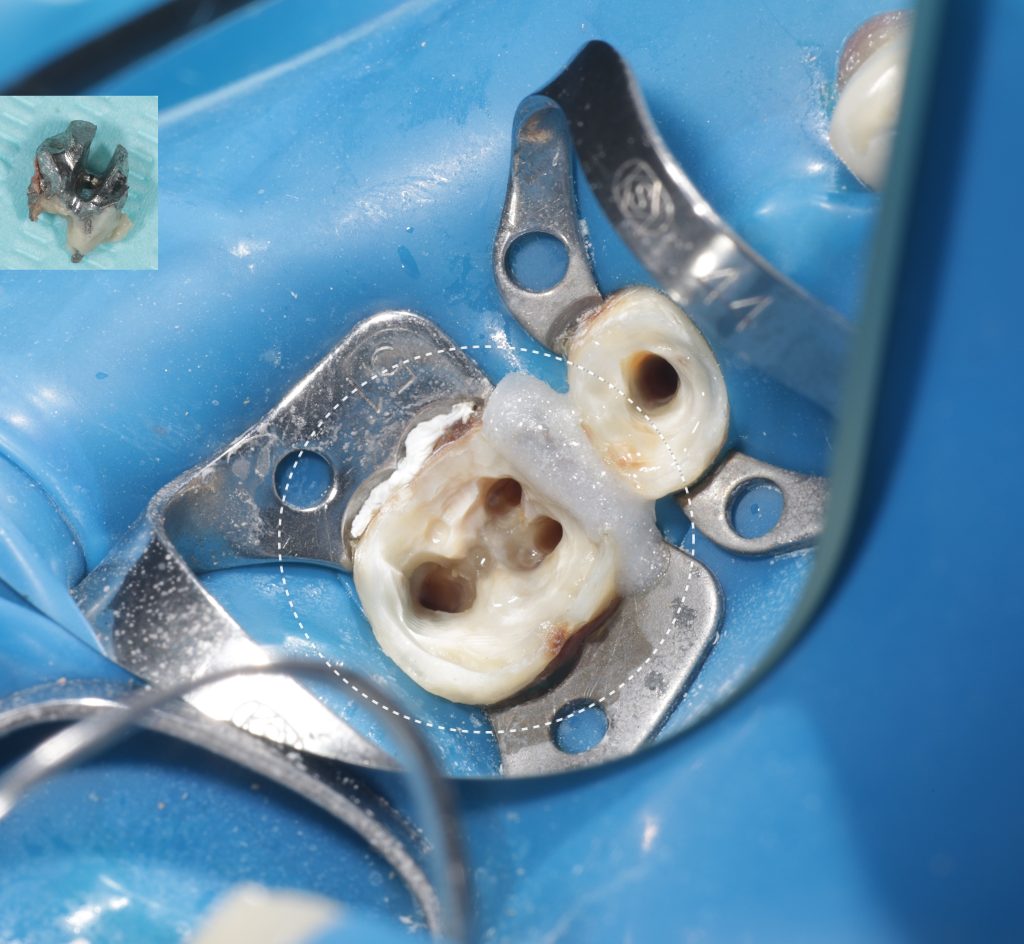

Проведено повторное эндодонтическое лечение зуба 3.6. Успешно извлечена культевая вкладка